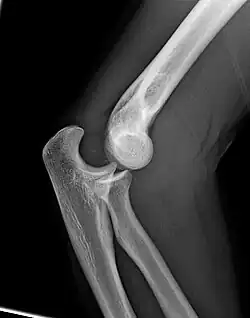

Right: AP X ray of a dislocated right elbow

There are three bones at the elbow joint, and any combination of these bones may be involved in a fracture of the elbow. Patients who are able to fully extend their arm at the elbow are unlikely to have a fracture (98% certainty) and an X-ray is not required as long as an olecranon fracture is ruled out.[27] Acute fractures may not be easily visible on X-ray.[28]

Dislocation

Elbow dislocations constitute 10% to 25% of all injuries to the elbow. The elbow is one of the most commonly dislocated joints in the body, with an average annual incidence of acute dislocation of 6 per 100,000 persons.[30] Among injuries to the upper extremity, dislocation of the elbow is second only to a dislocated shoulder. A full dislocation of the elbow will require expert medical attention to re-align, and recovery can take approximately 6 weeks.